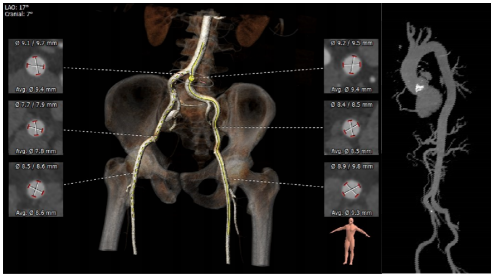

根部评估

Type1型二叶式主动脉瓣,L-N融合,主动脉瓣环周长83.8mm,平均周长径26.8mm。瓦式窦可。左冠开口高度16.3mm,右冠开口高度25.6mm。

弓部及入路评估

主动脉弓部夹角略锐,角度84度,最短距离70.3mm,必要时可采取Snare辅助过弓;外周入路血管条件良好,无钙化,未发现其他血管病变,双侧入路血管管径可。